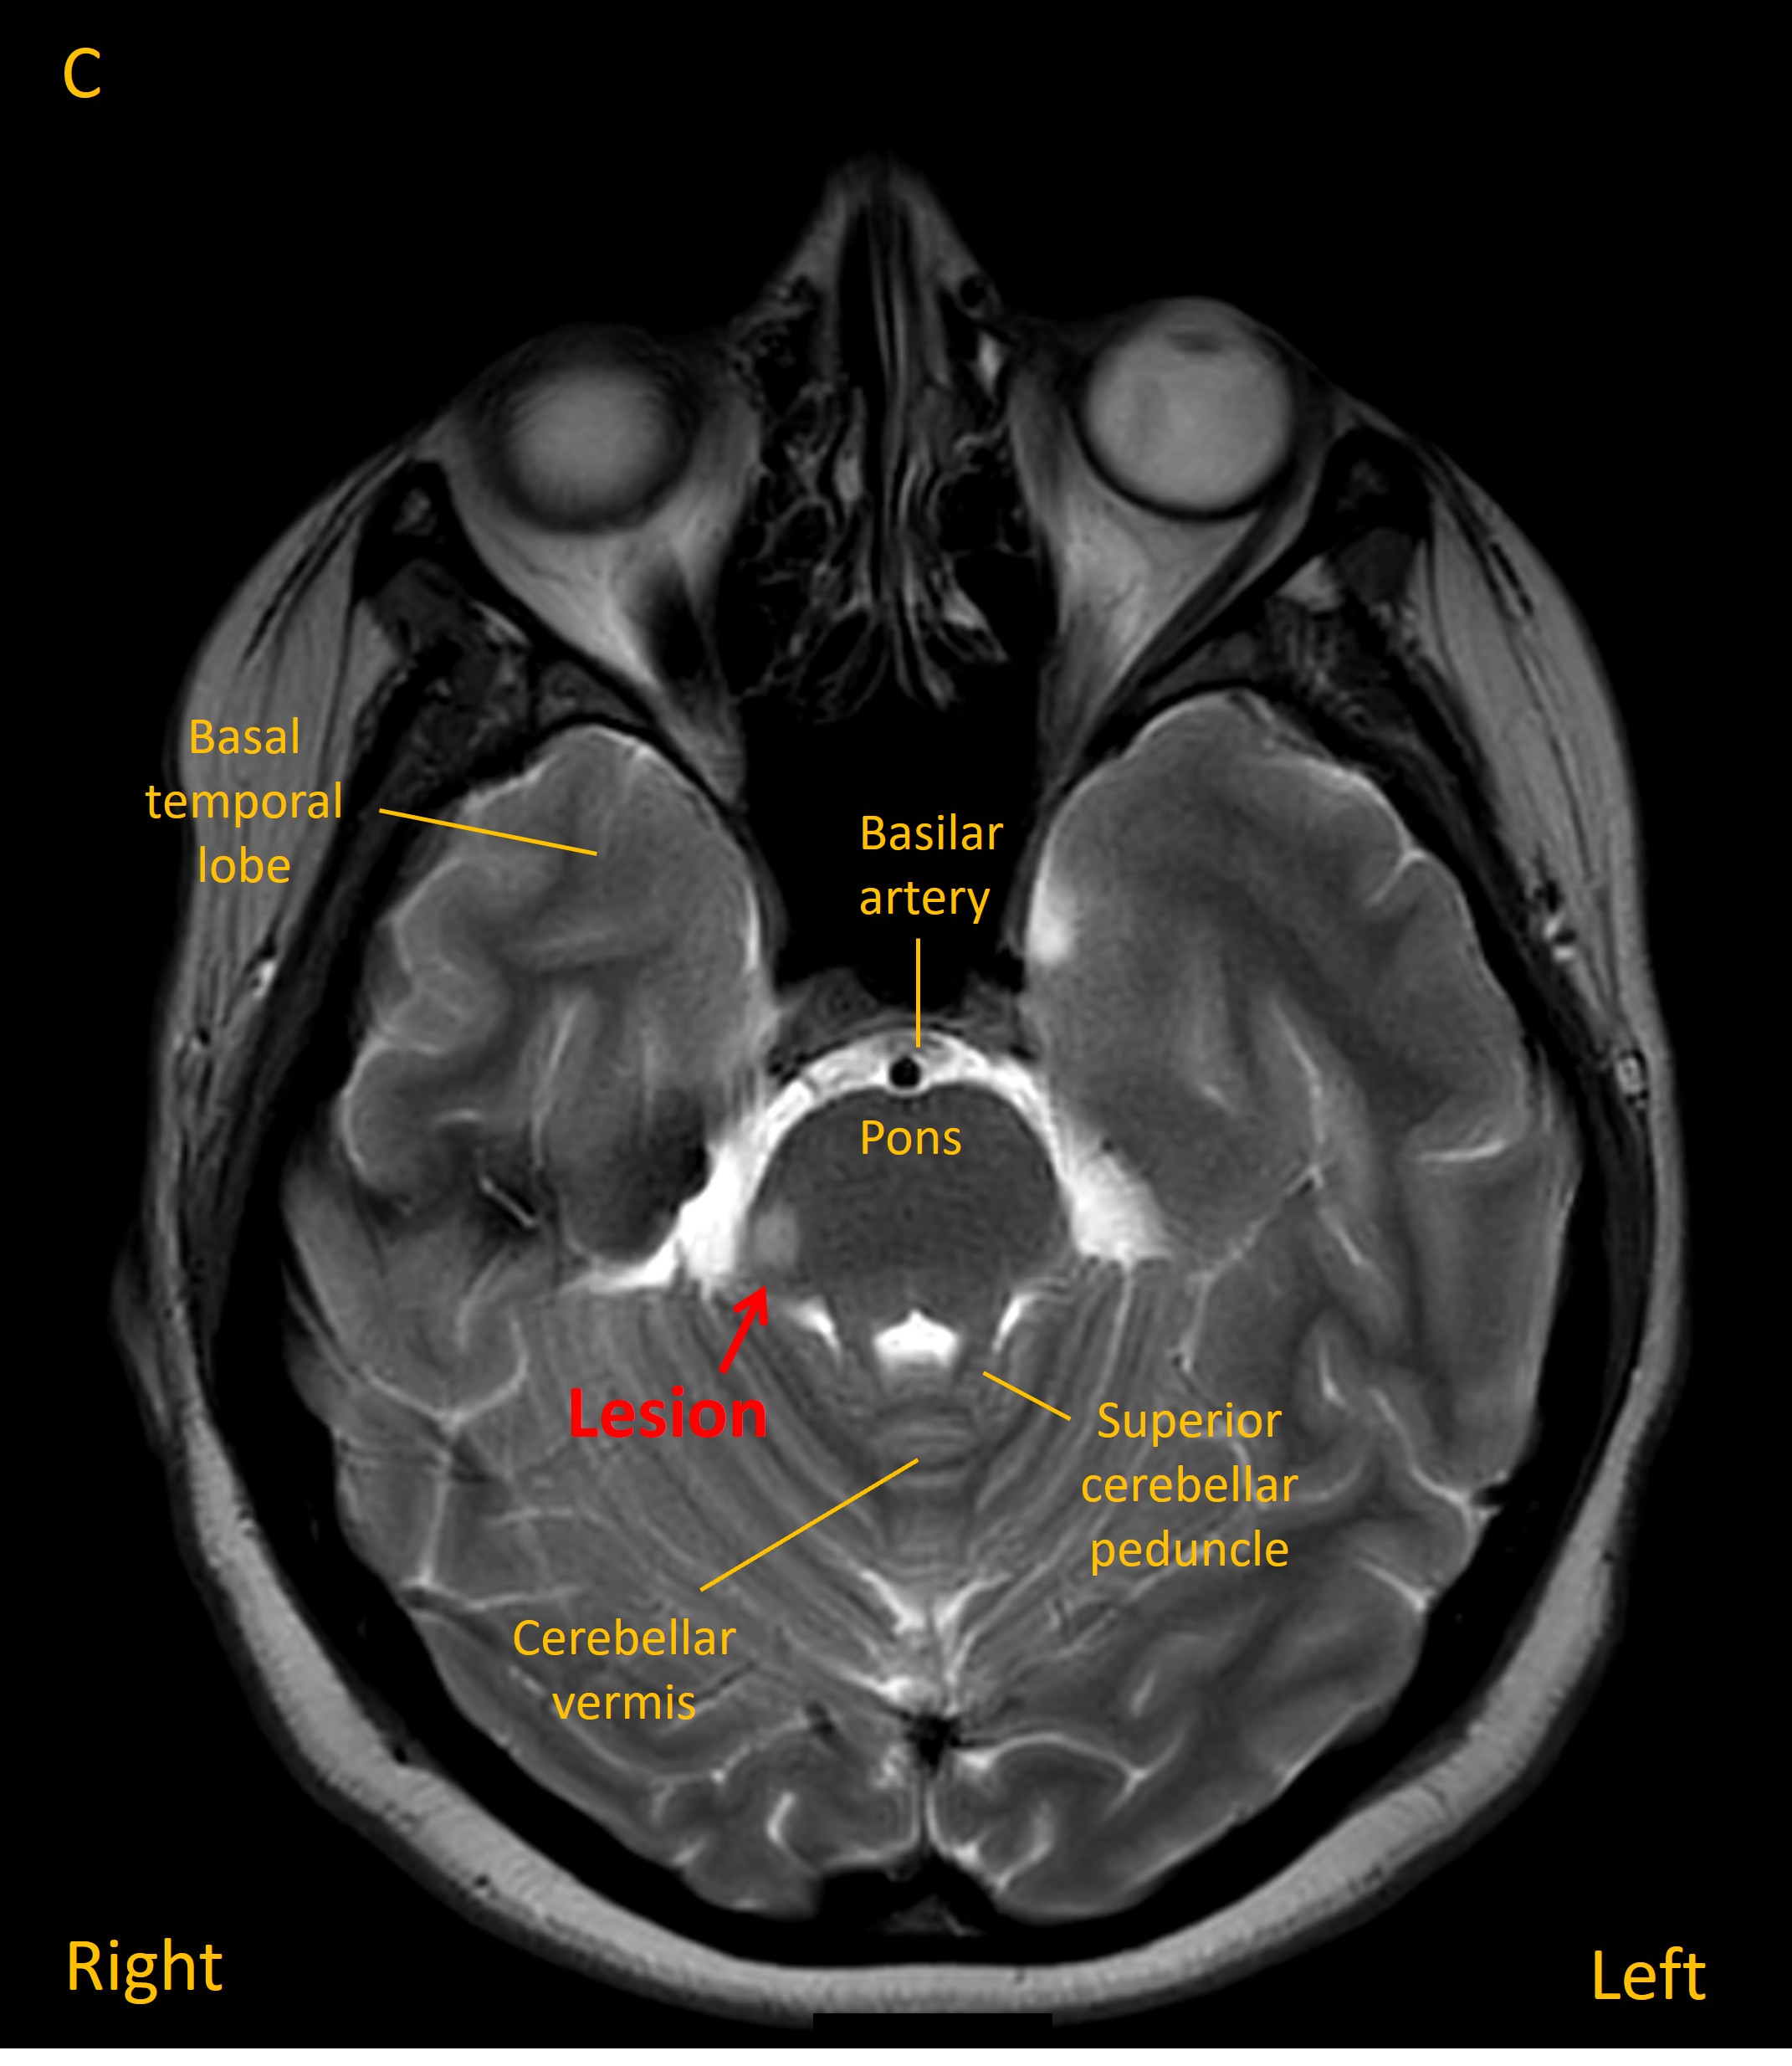

However, two months later she reported deterioration in her gait, with falls at home. On examination she had a cautious-looking gait, taking small steps, and bilateral heel-shin ataxia on examination, but no focal signs otherwise. An MRI showed a new lesion in the right dorsolateral superior pons. The previous cerebellar lesion was still present, but less hyperintense than earlier. Additional small lesions were noted in the periventricular region.

On the basis of a new demyelinating lesion separated across time, additional clinically-silent new periventricular lesions appearing on the MRI, and the CSF analysis, she was diagnosed with MS. Given the two events a short number of weeks apart, the diagnosis was of rapidly-evolving MS, so she was started on a highly-effective oral treatment. Her condition was stable on follow-up over the following 2 years.